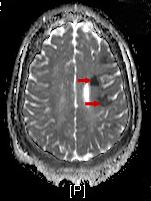

Findings of an MRI scan of the head were significant for multifocal bilateral subacute infarcts, predominantly scattered throughout the left cerebral hemisphere with superimposed multifocal remote infarcts, and vessel occlusion (Figures 1-3).

Figure 2